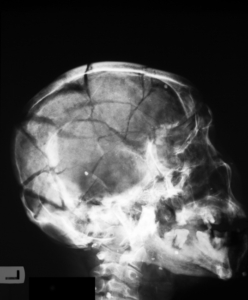

The skull serves as a protective shell for the brain. Still, even this strong structure can fracture under severe impact, often resulting in traumatic brain injuries that require urgent medical and legal attention.

Skull fractures are generally classified into several types:

- Linear fractures: Simple cracks in the bone that typically heal with rest and observation.

- Depressed fractures: Sections of the skull are pushed inward toward the brain, often requiring surgical intervention.

- Basilar fractures: Occur at the base of the skull and may affect nerves or cause cerebrospinal fluid leakage.

- Compound fractures: Breaks where both the skin and bone are penetrated, significantly increasing the risk of infection.